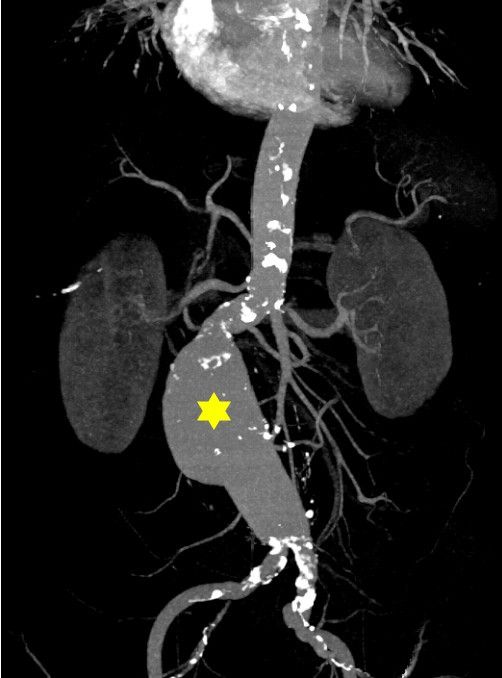

ÃÖ±Ù ±¹³» ¿¬±¸¿¡¼ Á¶±â Æó°æÀÌ ¸¸¼ºÁúȯ»Ó ¾Æ´Ï¶ó »ý¸í¿¡ Á÷Á¢ À§ÇùÀÌ µÇ´Â ¡®º¹ºÎ ´ëµ¿¸Æ·ù¡¯ À§ÇèÀ» ³ôÀÌ´Â °ÍÀ¸·Îµµ ³ªÅ¸³µ´Ù.

¡®¹î¼Ó ½ÃÇÑÆøÅº¡¯À¸·Î ºÒ¸®´Â º¹ºÎ ´ëµ¿¸Æ·ù´Â ÅÍÁö¸é »ç¸Á·üÀÌ 80~90%¿¡ ´ÞÇÑ´Ù. º´¿ø µµÂø Àü¿¡ ´ëºÎºÐ »ý¸íÀ» ÀҰųª ³»¿øÇÏ´õ¶óµµ ¼ö¼ú¹æ¿¡ µé¾î°¡±â Àü¿¡ »ç¸ÁÇÒ ¼ö ÀÖ´Ù. ÆÄ¿µÇ±â Àü¿¡ ¹ß°ßÇØ ¼ö¼ú¹ÞÀ¸¸é ÇÕº´Áõ ¹ß»ýÀº 3~6%¿¡ ±×Ä£´Ù. ÀÌ¿¡ µû¶ó Èí¿¬, °íÇ÷¾Ð µî ÀÌ¹Ì ¹àÇôÁø À§Çè¿äÀΰú ´õºÒ¾î Á¶±â Æó°æÀ» ¿©¼º º¹ºÎ ´ëµ¿¸Æ·ùÀÇ ¼±º°°Ë»ç ±âÁØ¿¡ Æ÷ÇÔÇØ¾ß ÇÑ´Ù´Â ÁöÀûÀÌ ³ª¿Â´Ù.

ÀºÆò¼º¸ðº´¿ø Ç÷°üÀ̽Ŀܰú ±è¹ÌÇü¡¤È²Á¤±â ±³¼öÆÀÀº ±¹Á¦ ÇмúÁö(Journal of Vascular Surgery)¡¯ ÃֽйßÇ¥ ³í¹®À» ÅëÇØ Á¶±â Æó°æÀÌ º¹ºÎ ´ëµ¿¸Æ·ùÀÇ »õ·Î¿î À§Çè ÀÎÀÚÀÓÀ» óÀ½À¸·Î ¹àÇô³Â´Ù.

¿¬±¸ÆÀÀº 2009³â ±¹°¡°Ç°°ËÁøÀ» ¹ÞÀº 40¼¼ ÀÌ»ó ¿©¼º 310¸¸¸í Áß ¼ö¼úÀ̳ª À¯¹æ¾Ï È£¸£¸ó Ä¡·á·Î ÀÎÇÑ Æó°æ µîÀ» Á¦¿ÜÇÑ ÀÚ¿¬ Æó°æ ¿©¼º 139¸¸¸íÀ» 2019³â±îÁö 10³â°£ ÃßÀû °üÂûÇß´Ù. °ËÁø ´ç½Ã 40¼¼ ÀÌÀü¿¡ Æó°æÇß´Ù°í ¹àÈù °æ¿ì Á¶±â Æó°æ±ºÀ¸·Î ºÐ·ùÇß´Ù. ¿¬±¸ °á°ú ÇØ´ç ±â°£ º¹ºÎ ´ëµ¿¸Æ·ù Áø´ÜÀÚ 3629¸í Áß Á¶±â Æó°æ ¿©¼ºÀº 102¸í(2.81%)À̾ú´Ù. ÀÌ´Â º¹ºÎ ´ëµ¿¸Æ·ù ¹ÌÁø´Ü ¿©¼º Áß Á¶±â Æó°æ ºñÀ²(1.78%)À» ÈξÀ ¿ôµµ´Â °ÍÀÌ´Ù. ¶Ç 40¼¼ ÀÌÀü Æó°æ ¿©¼ºÀº 55¼¼ ÀÌÈÄ Æó°æ ¿©¼ºº¸´Ù º¹ºÎ ´ëµ¿¸Æ·ù À§ÇèÀÌ 23% ³ô¾Ò´Ù. Æò»ý ¿ù°æ ±â°£ÀÌ 30³â ¹Ì¸¸ÀÎ ¿©¼ºÀº 40³â ÀÌ»ó ¿©¼ºº¸´Ù º¹ºÎ ´ëµ¿¸Æ·ù À§ÇèÀÌ 20% Áõ°¡Çß´Ù. ¿©¼º È£¸£¸ó ³ëÃ⠱ⰣÀÌ ÂªÀ»¼ö·Ï º¹ºÎ ´ëµ¿¸Æ·ù ¹ß»ý °¡´É¼ºÀÌ Ä¿Áö´Â °ÍÀÌ´Ù. ±è¹ÌÇü ±³¼ö´Â ¡°¿©¼º È£¸£¸óÀº Ç÷°üÀ» º¸È£ÇÏ´Â ¿ªÇÒÀ» Çϴµ¥ Á¶±â Æó°æÀ¸·Î ÀÌ·± È¿°ú°¡ »ç¶óÁö±â ¶§¹®À¸·Î º¸Àδ١±°í ¼³¸íÇß´Ù.

Ñûº¸´Ù º¹ºÎ ´ëµ¿¸Æ·ù À§Çè 4¹è ¡è

º¹ºÎ ´ëµ¿¸Æ·ù´Â ¸ö¼ÓÀÇ °¡Àå Å« Ç÷°üÀÎ ´ëµ¿¸ÆÀÌ ¿ø·¡ Á÷°æº¸´Ù 50% ÀÌ»ó Ä¿Áö´Â »óÅ´Ù. ¡®·ù(×»)¡¯´Â Ç÷°üÀÌ È¤Ã³·³ ºÎÇ®¾îÁø »óŸ¦ ¸»ÇÑ´Ù. Á¤»ó ´ëµ¿¸Æ Á÷°æÀº 2~2.5§¯Àε¥, 5§¯ ÀÌ»ó ºÎÇ®¸é ÅÍÁú À§ÇèÀÌ ³ô¾Æ ¼ö¼úÀÌ ÇÊ¿äÇÏ´Ù. ´ëµ¿¸Æ Á÷°æÀÌ 5§¯ ÀÌ»óÀÌ¸é ÆÄ¿ À§ÇèÀÌ 1³â¿¡ 1~5%, 6§¯ ÀÌ»óÀ̸é 10%, 7§¯ ÀÌ»óÀ̸é 20%, 8§¯ ÀÌ»óÀ̸é 40%·Î Á¡Á¡ ³ô¾ÆÁø´Ù. µû¶ó¼ ÆÄ¿ Àü¿¡ ¹ß°ßÇØ Ä¡·áÇÏ´Â °ÍÀÌ ¹«¾ùº¸´Ù Áß¿äÇÏ´Ù.

±è ±³¼ö´Â ¡°º¹ºÎ ´ëµ¿¸Æ·ù´Â ÆÄ¿ÀÌ µÇ³Ä ¾È µÇ³Ä¿¡ µû¶ó ȯÀÚ ¿¹Èİ¡ ±Ø¸íÇÏ°Ô °¥¸®´Â ÁúȯÀ̹ǷΠ¼±º°°Ë»ç°¡ ÇÊ¿äÇѵ¥µµ ÇöÀç ºñ¿ë È¿°ú¼º ¶§¹®¿¡ ½ÃÇàµÇÁö ¸øÇϰí ÀÖ´Ù¡±°í ¸»Çß´Ù. ¹Ì±¹¡¤À¯·´¿¡¼± 65¼¼ ÀÌ»ó, Èí¿¬·ÂÀ» °¡Áø ³²¼º¿¡¼± ¼±º°°Ë»ç°¡ ÀÌ·ïÁö°í ÀÖ´Ù. Çѱ¹Àº ³²¼º°ú ¿©¼º ¸ðµÎ¿¡ ¼±º°°Ë»ç¸¦ ÇÏÁö ¾Ê°í ÀÖ´Ù.

´õ±¸³ª ¿©¼ºÀº ³²¼ºº¸´Ù º¹ºÎ ´ëµ¿¸Æ·ùÀÇ ÆÄ¿ À§ÇèÀÌ 4¹è ´õ ³ô°í ¿¹Èİ¡ ºÒ·®ÇÏ´Ù. ¿©¼ºÀº Á¤»ó ´ëµ¿¸ÆÀÇ Å©±â ÀÚü°¡ À۱⠶§¹®¿¡ ³²¼º°ú °°Àº ±âÁرîÁö Ä¿Áö¸é ÅÍÁú °¡´É¼ºÀÌ Å©´Ù. ȲÁ¤±â ±³¼ö´Â ¡°Á¶±â Æó°æ ¿©¼ºÀº ±âÁ¸ÀÇ °íÀ§Çè ÀÎÀÚ(Èí¿¬, °íÇ÷¾Ð µî)¸¦ °¡Áø À̵é°ú ÇÔ²² ¼±º°°Ë»ç ´ë»ó¿¡ Æ÷ÇÔÇÒ Çʿ䰡 ÀÖ´Ù¡±°í ÁöÀûÇß´Ù. ¾Æ¿ï·¯ Á¶±â Æó°æÇÑ °æ¿ì¶ó¸é °Ç°ÇÑ ½Ä»ýȰ, üÁß °ü¸®, À¯»ê¼Ò ¿îµ¿ µî ¼öÄ¢À» ´õ öÀúÈ÷ ÁöŰ°í ´ëµ¿¸Æ ÃÊÀ½ÆÄ °Ë»ç¸¦ ÇÑ ¹ø °í·ÁÇØ º¼ Çʿ䰡 ÀÖ´Ù. ±è ±³¼ö´Â ¡°ÀϹÝÀû À¯º´ ³ªÀ̳ª ÁøÇà ¼Óµµ¸¦ ±Ù°Å·Î º¼ ¶§ 60¼¼ °æ¿¡ ÇÑ ¹ø ¹Þ¾Æº¸°í °üÂûµÇÁö ¾ÊÀ¸¸é Áֱ⸦ µÎ°í ¹Ýº¹ °Ë»ç¸¦ ÇØ º¸¸é ÁÁ°Ú´Ù¡±°í ±Ç°íÇß´Ù.